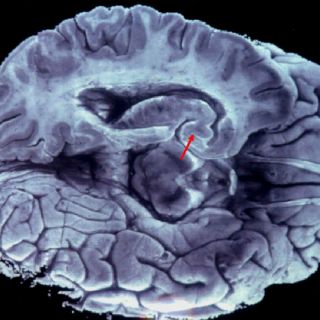

Aumento de la contaminación eleva número de ataques cerebrales

MADRID, ESPAÑA (17/FEB/2016).- El aumento de la

contaminación y la baja calidad el aire en general influye en el número de ataques cerebrales, según un estudio sobre la interacción entre la polución y la prevalencia de esta enfermedad, que analiza también el efecto potencial de la temperatura.